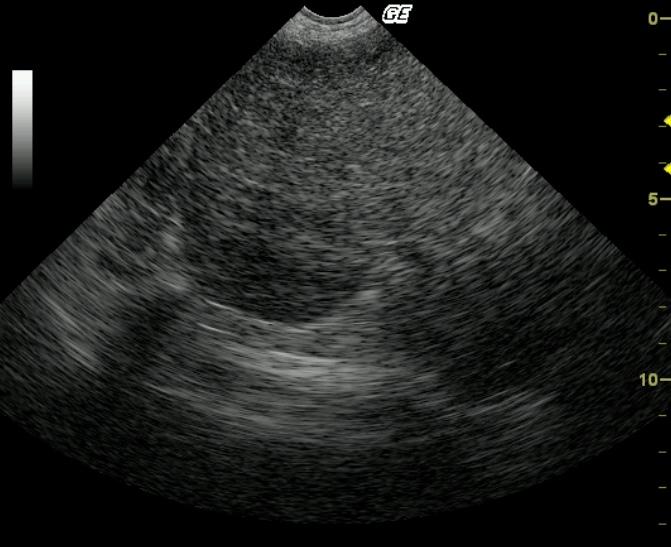

Long-axis left lateral lobar view reveals an ill-defined, lobulated, serosa-displacing, echogenic parenchymal swelling or mass. Note the smooth swollen serosal contour of the left lateral liver lobe.

Moderate hepatocellular swelling and glycogen accumulation.

14-gauge US-guided biopsy revealed moderate hepatocellular swelling and glycogen accumulation.